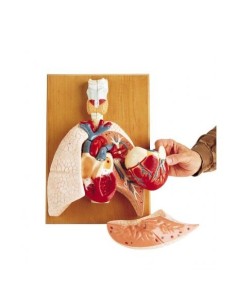

Du crâne en 22 parties à verrouillage magnétique aux modèles de colonne vertébrale, des modèles d'articulation aux modèles de cœur, chaque pièce de notre collection est conçue pour une immersion totale dans l'étude de l'anatomie humaine. Nos modèles, réalisés à partir de scans d'os réels, garantissent une expérience tactile authentique et une fidélité de poids presque identique aux originaux.